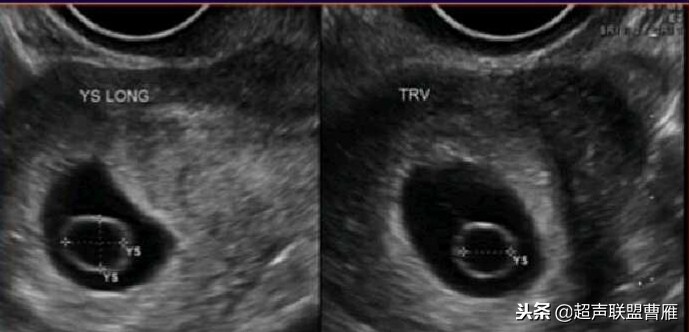

超声检查卵黄囊出现之后到孕龄12周之间多能见到卵黄囊,直径在0.3-0.5cm之间。卵黄囊的直径与形态正常是胚胎发育良好的标志。

最大卵黄囊(5周)(12周)

卵黄囊11*6.9mm 大卵黄囊

卵黄囊 羊膜囊 小胎儿雏形 (卵黄囊直径8.5mm)

卵黄囊过小2mm